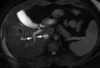

Head And Neck Flashcards

(292 cards)